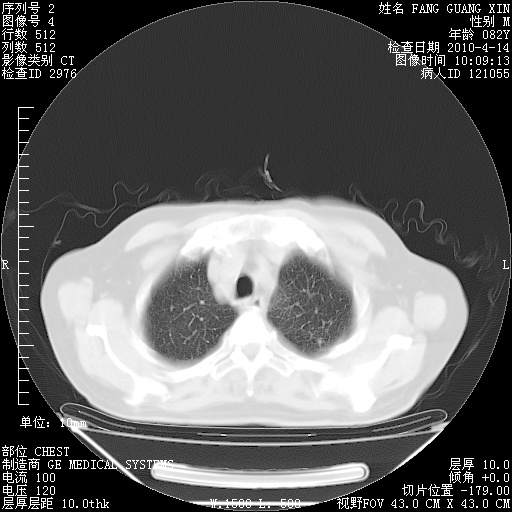

4月14日肺部CT

肺部CT平扫未见异常。